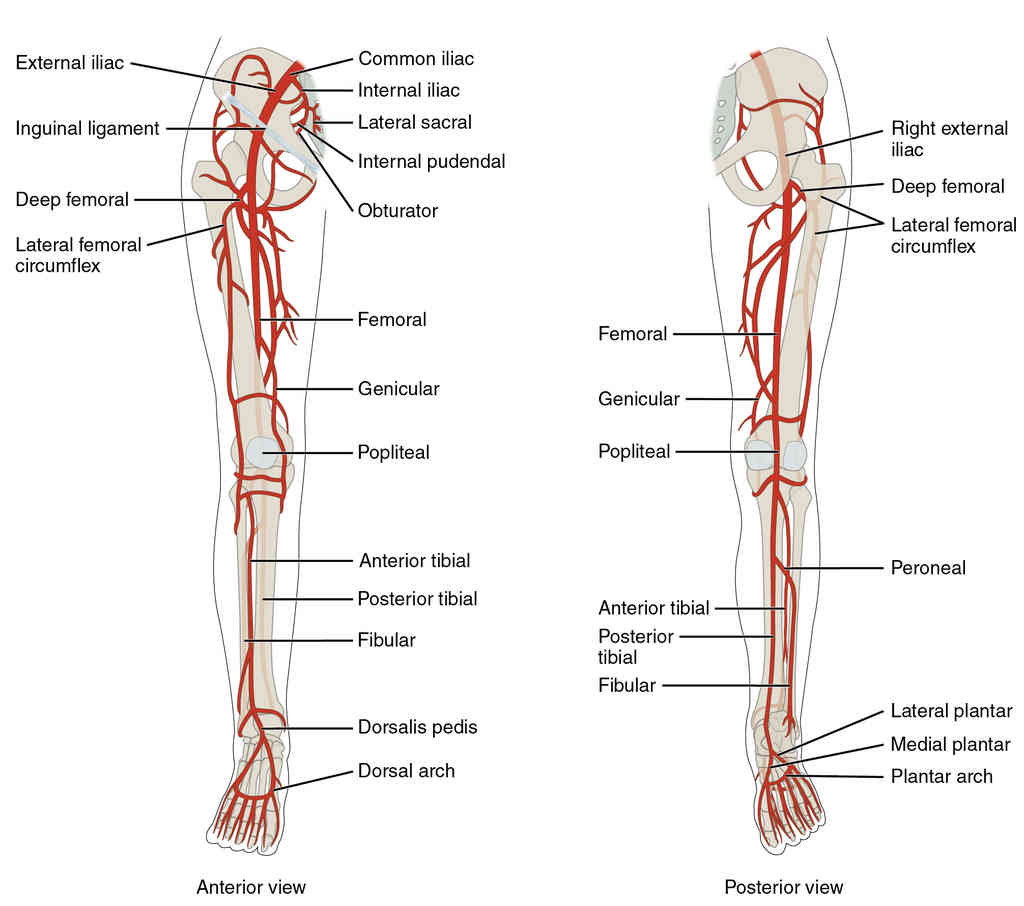

This page is under construction. For now, it is just a resource of the images found in the OpenStax Anatomy and Physiology Handbook. It wil slowly change into a revision tool. Each slide has a number. Use this to refer to the slide. When completed, it will have an unlabelled section, with labelled slides in parallel. On the unlabelled slides, write your answer and use the labelled slide to assess yourself. Keep track by also noting the number on each slide. Improvement at each attempt is important, more so than full marks on a first attempt.